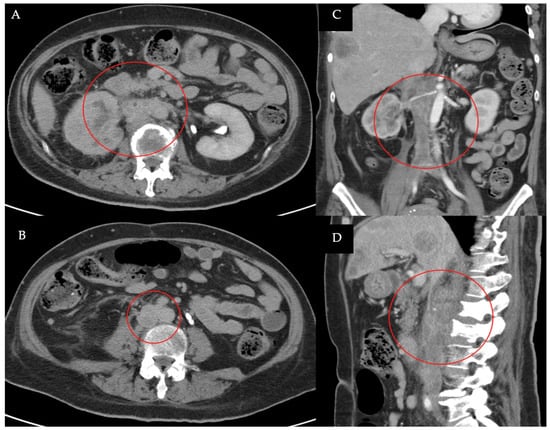

2. Detailed Case Description